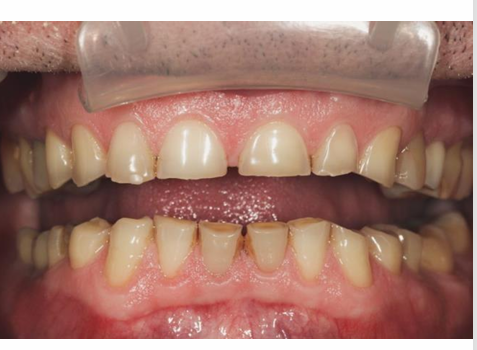

MFD EXAMS /23 6 1234567891011121314151617181920212223 You have 30 min to complete this exam. The timer will start once you begin Attention: Only a few minutes left! Please submit your answers soon. MFD 1 Get a quick sneak peek before the real exam !This trial quiz is designed to show you the question style, difficulty level, and how the options will appear on the platform. 1 / 23 1. What is the lethal dose and toxic dose of fluoride, management? Check 2 / 23 2. What the advantage of silver diamine over other methods and disadvantages ? Check 3 / 23 3. Method of topical fluoride application with concentration ? Check 4 / 23 4. What will happen if left untreated? Check 5 / 23 5. What changes that will happen if the habit stopped? Check 6 / 23 6. Give 3 of your initial stage of treatment? Check 7 / 23 7. What are the causes? Check 8 / 23 8. What is this? Check 9 / 23 9. Then they specified the type of pain and asked about the diagnosis Check 10 / 23 10. What other tests to check vitality of the pulp? Check 11 / 23 11. What are the factors will govern the Rx of Posterior cross bite ? Check 12 / 23 12. What are the factors that govern the treatment of anterior cross bite? Check 13 / 23 13. Name the appliance that you can use to treat this case? Check 14 / 23 14. Name 3 causes? Check 15 / 23 15. Name the most important clinical diagnostic information you need to know. (check RCSI intensive course )? Check 16 / 23 16. What do you see? Check 17 / 23 17. What is your treatment? Check 18 / 23 18. Name the investigations needed? Check 19 / 23 19. causes for gingival enlargement ? Check 20 / 23 20. What is the common side effect of this drug? Check 21 / 23 21. Name the drug that he may take to treat this condition? Check 22 / 23 22. The patient may have what? Check 23 / 23 23. What is this clinical condition? Check /31 2 12345678910111213141516171819202122232425262728293031 You have 30 min to complete this exam. The timer will start once you begin Attention: Only a few minutes left! Please submit your answers soon. MFD 2 Get a quick sneak peek before the real exam !This trial quiz is designed to show you the question style, difficulty level, and how the options will appear on the platform. 1 / 31 1. Mention 2 fixed space maintainers and 2 removable space maintainers other from mentioned : Check 2 / 31 2. Other space maintenance used for child lost primary second molar E before the eruption of the permanent molars ? Check 3 / 31 3. What are the difference between nance appliance and Transpalatal arch Check 4 / 31 4. What material used to attach band? Check 5 / 31 5. What instruction you give to patient? Check 6 / 31 6. Name other fixed space maintainer used in upper jaw and mechanism of their action? Check 7 / 31 7. What component of this appliance? Check 8 / 31 8. What is this appliance , for what its used ? Check 9 / 31 9. Treatment? Check 10 / 31 10. Define Abrasion and Erosion? Check 11 / 31 11. What does this picture show? Check 12 / 31 12. what investigations you can do ? Check 13 / 31 13. Drugs can lead to lichenoid reaction Check 14 / 31 14. What extra oral features in “ Lichenoid reaction )? Check 15 / 31 15. What microscopical features of it ( licheonoid reaction )? Check 16 / 31 16. Definitive diagnosis ? Check 17 / 31 17. Mention type of suggested biopsy ? Check 18 / 31 18. Mention 4 differential diagnosis ? Check 19 / 31 19. Mention 4 questions you will ask the patient ? Check 20 / 31 20. Give 4 intraoral decription of what you see ? Check 21 / 31 21. What the other surgery can be performed to make prothesis? Check 22 / 31 22. Can this tooth stand with fixed prothesis? (in the opg )à taken from Malek file ? Check 23 / 31 23. Radiograph of missing multiple teeth consider it according to Antes law? ON which tooth you will make Abutment ? Check 24 / 31 24. What is Antes law? Check 25 / 31 25. What is best one to use as abutment in fixed prosthesis A or B? Check 26 / 31 26. What relevance of this picture? Check 27 / 31 27. What’s complication of doing surgery in this area floor of mouth? Check 28 / 31 28. Other 2 radiograph needed in diagnosis? Check 29 / 31 29. Give 4 differential diagnosis? Check 30 / 31 30. What can you see ? Check 31 / 31 31. What is the name of radiograph? Check Your score is /30 1 123456789101112131415161718192021222324252627282930 You have 30 min to complete this exam. The timer will start once you begin Attention: Only a few minutes left! Please submit your answers soon. MFD 3 Get a quick sneak peek before the real exam !This trial quiz is designed to show you the question style, difficulty level, and how the options will appear on the platform. 1 / 30 1. Treatment? Check 2 / 30 2. Histopathology? Check 3 / 30 3. Differential diagnosis Check 4 / 30 4. Clinical features’? Check 5 / 30 5. Patient said, this lesion is very frequent, why? Check 6 / 30 6. What are the causes for ulcers? Check 7 / 30 7. Patient have other signs like uveitis ,Genital ulcerations which syndrome he had ? Check 8 / 30 8. Name of the lesion ? Check 9 / 30 9. Mention some TMJ movement ? Check 10 / 30 10. Blood supply ? Check 11 / 30 11. Nerve supply ? Check 12 / 30 12. Which muscles close? Check 13 / 30 13. Action of open and open wide? Check 14 / 30 14. Why it’s Atypical joint ? Check 15 / 30 15. Name of the ligaments ? Check 16 / 30 16. What would be your management? Check 17 / 30 17. Bacteria involved Check 18 / 30 18. Which type of Periodontitis? Check 19 / 30 19. Treatment? Check 20 / 30 20. Histopathology? Check 21 / 30 21. Differential diagnosis? Check 22 / 30 22. Clinical features? Check 23 / 30 23. What are the time frames for making a complaint? Check 24 / 30 24. What are the 3 points related to negligence? Check 25 / 30 25. Who is allowed access to the patient records? Check 26 / 30 26. How to differentiate if it is upper or lower motor neuron lesion? Check 27 / 30 27. Management? Check 28 / 30 28. What are the causes? Check 29 / 30 29. What should you advise the patient to do? Check 30 / 30 30. What is this lesion? Check Your score is /24 1 123456789101112131415161718192021222324 You have 30 min to complete this exam. The timer will start once you begin Attention: Only a few minutes left! Please submit your answers soon. MFD 4 Get a quick sneak peek before the real exam !This trial quiz is designed to show you the question style, difficulty level, and how the options will appear on the platform. 1 / 24 1. What does MRONJ stands for? Check 2 / 24 2. Give definition for MRONJ Check 3 / 24 3. For what medical problems these medications are used? Check 4 / 24 4. Stages of MRONJ 3 Check 5 / 24 5. What’s this appliance? Check 6 / 24 6. At what age is it used? Check 7 / 24 7. What type of malocclusion is it used to treat? Check 8 / 24 8. What changes will produce? (4 options) Check 9 / 24 9. Disadvantages? Check 10 / 24 10. Why is it flabby tissue? Check 11 / 24 11. what is this condition called? Check 12 / 24 12. Causes ? Check 13 / 24 13. Clinical Features ? Check 14 / 24 14. How to avoid it ? Check 15 / 24 15. Management? Check 16 / 24 16. Ideal post length and width Check 17 / 24 17. Definition of Ferrule it’s the Check 18 / 24 18. What is the importance of the ferrule effect ? Check 19 / 24 19. Describe the radiolucency? Check 20 / 24 20. Give 6 differential diagnosis? Check 21 / 24 21. Give 5 radiographical features? Check 22 / 24 22. What is the difference between incisional and excisional biopsy? Check 23 / 24 23. What other 2 plain radiographs we can we can take? Check 24 / 24 24. ALARA? Check Your score is /22 1 12345678910111213141516171819202122 You have 30 min to complete this exam. The timer will start once you begin Attention: Only a few minutes left! Please submit your answers soon. MFD 5 Get a quick sneak peek before the real exam !This trial quiz is designed to show you the question style, difficulty level, and how the options will appear on the platform. 1 / 22 1. . Types of external root resorption? Check 2 / 22 2. The cause of root resorption in the pic? Check 3 / 22 3. How you will treat it? Check 4 / 22 4. What is this probe? Check 5 / 22 5. What is the mark a ? Check 6 / 22 6. What is the mark b ? Check 7 / 22 7. What is the score from the given reading? Check 8 / 22 8. What is the treatment need of the patient according to the score? Check 9 / 22 9. What is the differential diagnosis ? Check 10 / 22 10. Four clinical features of the lesion? Check 11 / 22 11. Treatment ? Check 12 / 22 12. Describe what do you see? Check 13 / 22 13. Causes for it ? Check 14 / 22 14. Treatment ? Check 15 / 22 15. Picture of patient with Anaphylaxis…after taking Check 16 / 22 16. What is diagnosis? - Check 17 / 22 17. What a the signs of Anaphyalxis reactions ? Check 18 / 22 18. What first line of treatment? Dose? Route of Adminstration? Check 19 / 22 19. Other drug used? Check 20 / 22 20. What are expected complications if not treated ? Check 21 / 22 21. What precautions should be made to prevent anaphylaxis reaction ? - Check 22 / 22 22. Name 10 drug in emergency used with their route of Administration and their condition they use in? Check Your score is /36 1 123456789101112131415161718192021222324252627282930313233343536 You have 30 min to complete this exam. The timer will start once you begin Attention: Only a few minutes left! Please submit your answers soon. MFD 6 Get a quick sneak peek before the real exam !This trial quiz is designed to show you the question style, difficulty level, and how the options will appear on the platform. 1 / 36 1. . What are cases that you have to extract the primary tooth? Check 2 / 36 2. D. What are the indications for extraction? Check 3 / 36 3. What are your treatment options? Check 4 / 36 4. Investigations? Check 5 / 36 5. Type of trauma? Check 6 / 36 6. Patient diagnosed with sjorgen syndrome Histology ? - Check 7 / 36 7. Patient diagnosed with sjorgen syndrome Mention four blood investigations ? Check 8 / 36 8. Patient diagnosed with sjorgen syndrome Mention two sites where can we take the biopsy Check 9 / 36 9. Patient diagnosed with sjorgen syndrome How can you differentiate between primary and secondary ? Check 10 / 36 10. Gingival inflammation present in which syndrome Check 11 / 36 11. What is the treatment? Check 12 / 36 12. mention another connective tissue disease that can lead to lesions “ intraorally “ similar to the Lichen planus ? Check 13 / 36 13. what serious complication can arise from Erosive lichen planus ? Check 14 / 36 14. If it was atrophic lesion what histology might be seen ? Check 15 / 36 15. List the histological features of lichen planus ? Check 16 / 36 16. Lichen planus what dose it affect? Check 17 / 36 17. Age group commonly affected ? -ref SAQ Check 18 / 36 18. What are the clinical presentation ‘ types of lichen planus ‘ Check 19 / 36 19. What might you see in patient’s body that has a relation to this lesion? Check 20 / 36 20. What are the differential diagnoses? Check 21 / 36 21. Factors for platelet adhesion? Check 22 / 36 22. What can you see? Check 23 / 36 23. Other 2 process of hemostasis? Check 24 / 36 24. Two diseases in which they increase ? Check 25 / 36 25. Two diseases in which they decrease? Check 26 / 36 26. Medical term when they decrease? And if they increased Check 27 / 36 27. Function Check 28 / 36 28. Life span ? Check 29 / 36 29. From where they arise? Check 30 / 36 30. Normal number? Check 31 / 36 31. What are the function of the guiding plane ? Check 32 / 36 32. The success rate ? Check 33 / 36 33. Mention single extra preparation requirement for Resin bonded bridge in posterior teeth ? Check 34 / 36 34. Mention 5 preparation features of it? Check 35 / 36 35. Give two advantages of it ? Check 36 / 36 36. What’s the name of this prosthesis? Check Your score is /23 1 1234567891011121314151617181920212223 You have 30 min to complete this exam. The timer will start once you begin Attention: Only a few minutes left! Please submit your answers soon. MFD 7 Get a quick sneak peek before the real exam !This trial quiz is designed to show you the question style, difficulty level, and how the options will appear on the platform. 1 / 23 1. If the same scenario but the tooth is subluxated. What is the management? Check 2 / 23 2. Aim of this procedure Check 3 / 23 3. Steps to do this procedure? Check 4 / 23 4. Management? How to asses the vitality of the tooth Check 5 / 23 5. Mention factors that can affect the treatment plan ? Check 6 / 23 6. Identify the Kenneyd’s classification Check 7 / 23 7. Name its parts? Check 8 / 23 8. Uses of Surveyor Check 9 / 23 9. What is this ? Check 10 / 23 10. Criteria for hand piece sterilization Check 11 / 23 11. steps for wrapped instrument sterilization process ( ref : sterilization in SDCEP)? Check 12 / 23 12. What is the difference between sterilization and decontamination? Check 13 / 23 13. Optimal temperature & pressure & time for autoclave? Check 14 / 23 14. Difference between vacuum and non-vacuum autoclave in mechanism? Check 15 / 23 15. Optimum temperature? Check 16 / 23 16. Advantage of vaccum over non vaccum? Check 17 / 23 17. What is the significance of forehead wrinkling? Check 18 / 23 18. What is Ramsy haunt syndrome ? Rx ? and is it LMN or UMN ? Check 19 / 23 19. Enumerate 3 extracranial and intracranial causes for this ? Check 20 / 23 20. What are the branches of facial nerve? Check 21 / 23 21. Why do we suture the eye in a patient with Facial Palsy? Check 22 / 23 22. Differentiate between Upper and Lower Motor Neuron lesions? Check 23 / 23 23. What is shown in photograph? Check Your score is /27 0 123456789101112131415161718192021222324252627 You have 30 min to complete this exam. The timer will start once you begin Attention: Only a few minutes left! Please submit your answers soon. MFD 8 Get a quick sneak peek before the real exam !This trial quiz is designed to show you the question style, difficulty level, and how the options will appear on the platform. 1 / 27 1. Mention 4 diseases you would see in HIV Patients? Check 2 / 27 2. Give 2 differential diagnosis for this lesion? Check 3 / 27 3. Describe the lesion shown in Photograph B? Check 4 / 27 4. What is your diagnosis ? Check 5 / 27 5. Describe the lesion shown in Photograph A? Check 6 / 27 6. Disadvantages of gold ? Check 7 / 27 7. Ideal cement for All Porcelain? Check 8 / 27 8. Which cement would u use for high caries risk patient? Check 9 / 27 9. How much would you prepare for functional and non-functional cusps in Gold Crown? Check 10 / 27 10. what crown would you go for in bruxism patients out of these 3? Check 11 / 27 11. Name the 3 restorations? Check 12 / 27 12. After administering Local Anesthesia and deciding the choice of biopsy. What should be done before biopsying the lesion? Check 13 / 27 13. Name 2 systemic steroids with dosage you would recommend for this patient? Check 14 / 27 14. Name 2 topical steroids with dosage you would recommend for this patient? Check 15 / 27 15. What is your diagnosis? Check 16 / 27 16. Describe the lesion shown in photograph? Check 17 / 27 17. Name 5 options to increase retention and stability in class l Check 18 / 27 18. E. What is the function of the RPI system ? Check 19 / 27 19. What are the 2 disadvantages of the 2 restorations you mentioned? Check 20 / 27 20. What materials are your 2 restorations made of? Check 21 / 27 21. Other than implants what restoration would you place in this patient? Check 22 / 27 22. Which Kennedy’s classification is this? Check 23 / 27 23. Describe your management? Check 24 / 27 24. What may be the patient complaint? Check 25 / 27 25. What are the causes of this? Check 26 / 27 26. Describe what you see in the photograph? Check 27 / 27 27. which 4 examinations would you undertake? Check Your score is /31 0 12345678910111213141516171819202122232425262728293031 You have 30 min to complete this exam. The timer will start once you begin Attention: Only a few minutes left! Please submit your answers soon. MFD 9 Get a quick sneak peek before the real exam !This trial quiz is designed to show you the question style, difficulty level, and how the options will appear on the platform. 1 / 31 1. Describe what you see in the photograph? Check 2 / 31 2. Three other features of this syndrome ? Check 3 / 31 3. What is the medical condition associated with it “? Multiple OKC? Check 4 / 31 4. Where expansion occurs in the OKC ? Check 5 / 31 5. From which cells this lesion arises from? Check 6 / 31 6. What is your diagnosis? Check 7 / 31 7. What is the histopathology of the lesion shown in Histology slide? Check 8 / 31 8. Give 4 differential diagnosis? Check 9 / 31 9. What is the consequence of premature loss of deciduous teeth? Check 10 / 31 10. Identify those appliances and mention one use for each and mode of action? Check 11 / 31 11. What component of appliance no. 3 ? Check 12 / 31 12. How to overcome open bite disadvantage ? Check 13 / 31 13. What are Disadvantages of this appliance ? Check 14 / 31 14. What Ceph changes are expected while using this appliance ? Check 15 / 31 15. What is the construction of Twin Block Appliance? Check 16 / 31 16. What skeletal and dental changes are expected while using this appliance ? Check 17 / 31 17. What is the ideal age to treat this condition >? Check 18 / 31 18. Indications of the Twin Block Appliance? Two Check 19 / 31 19. Name the Appliance used to correct this? Check 20 / 31 20. What is the treatment? Check 21 / 31 21. How to prevent it Check 22 / 31 22. Mention three mechanisms of action of Fluoride? Check 23 / 31 23. What is the disease caused by excess Fluoride? Check 24 / 31 24. What are the risk factors associated with this patient? Check 25 / 31 25. Name the principal organism causing this? Check 26 / 31 26. what are the principles of the access cavity Check 27 / 31 27. What is your diagnosis? Check 28 / 31 28. What are principles of cavity preparation? Check 29 / 31 29. What is your Periapical diagnosis? Check 30 / 31 30. What is your Pulpal diagnosis? Check 31 / 31 31. Which test would you undertake? Check Your score is /21 0 123456789101112131415161718192021 You have 30 min to complete this exam. The timer will start once you begin Attention: Only a few minutes left! Please submit your answers soon. MFD 10 Get a quick sneak peek before the real exam !This trial quiz is designed to show you the question style, difficulty level, and how the options will appear on the platform. 1 / 21 1. Patient is 20 years old Mention two treatment options for this case ? Check 2 / 21 2. Patient is 20 years old What is the long term risk for not treating this case ? Check 3 / 21 3. Name of this appliance in the next picture? Check 4 / 21 4. What is the wire used ? Check 5 / 21 5. For which orthodontic cases this appliance is necessary ? Check 6 / 21 6. Why we use retainer ? Check 7 / 21 7. Describe what you see ? Check 8 / 21 8. Differential diagnosis:- Check 9 / 21 9. Name of those muscles ? Check 10 / 21 10. Name the Extrinsic muscles of the tongue? Check 11 / 21 11. . Which nerves innervate the Extrinsic muscles of the tongue?. Check 12 / 21 12. What is the somatic innervation of anterior 2/3 of tongue? Check 13 / 21 13. Which nerve supplies the posterior 1/3 of tongue?. Check 14 / 21 14. From which Pharyngeal arch posterior 1/3 derived from? Check 15 / 21 15. Mention the intrinsic muscle of the tongue ? Check 16 / 21 16. What is the name of this condition ? name the lesion on the skin ? Check 17 / 21 17. Mention 3 drugs that causing it ? Check 18 / 21 18. 2 infections associated with it Check 19 / 21 19. Mention 2 immediate treatment ? Check 20 / 21 20. Why this condition can be fatal ? Check 21 / 21 21. Which test would you undertake? Check Your score is